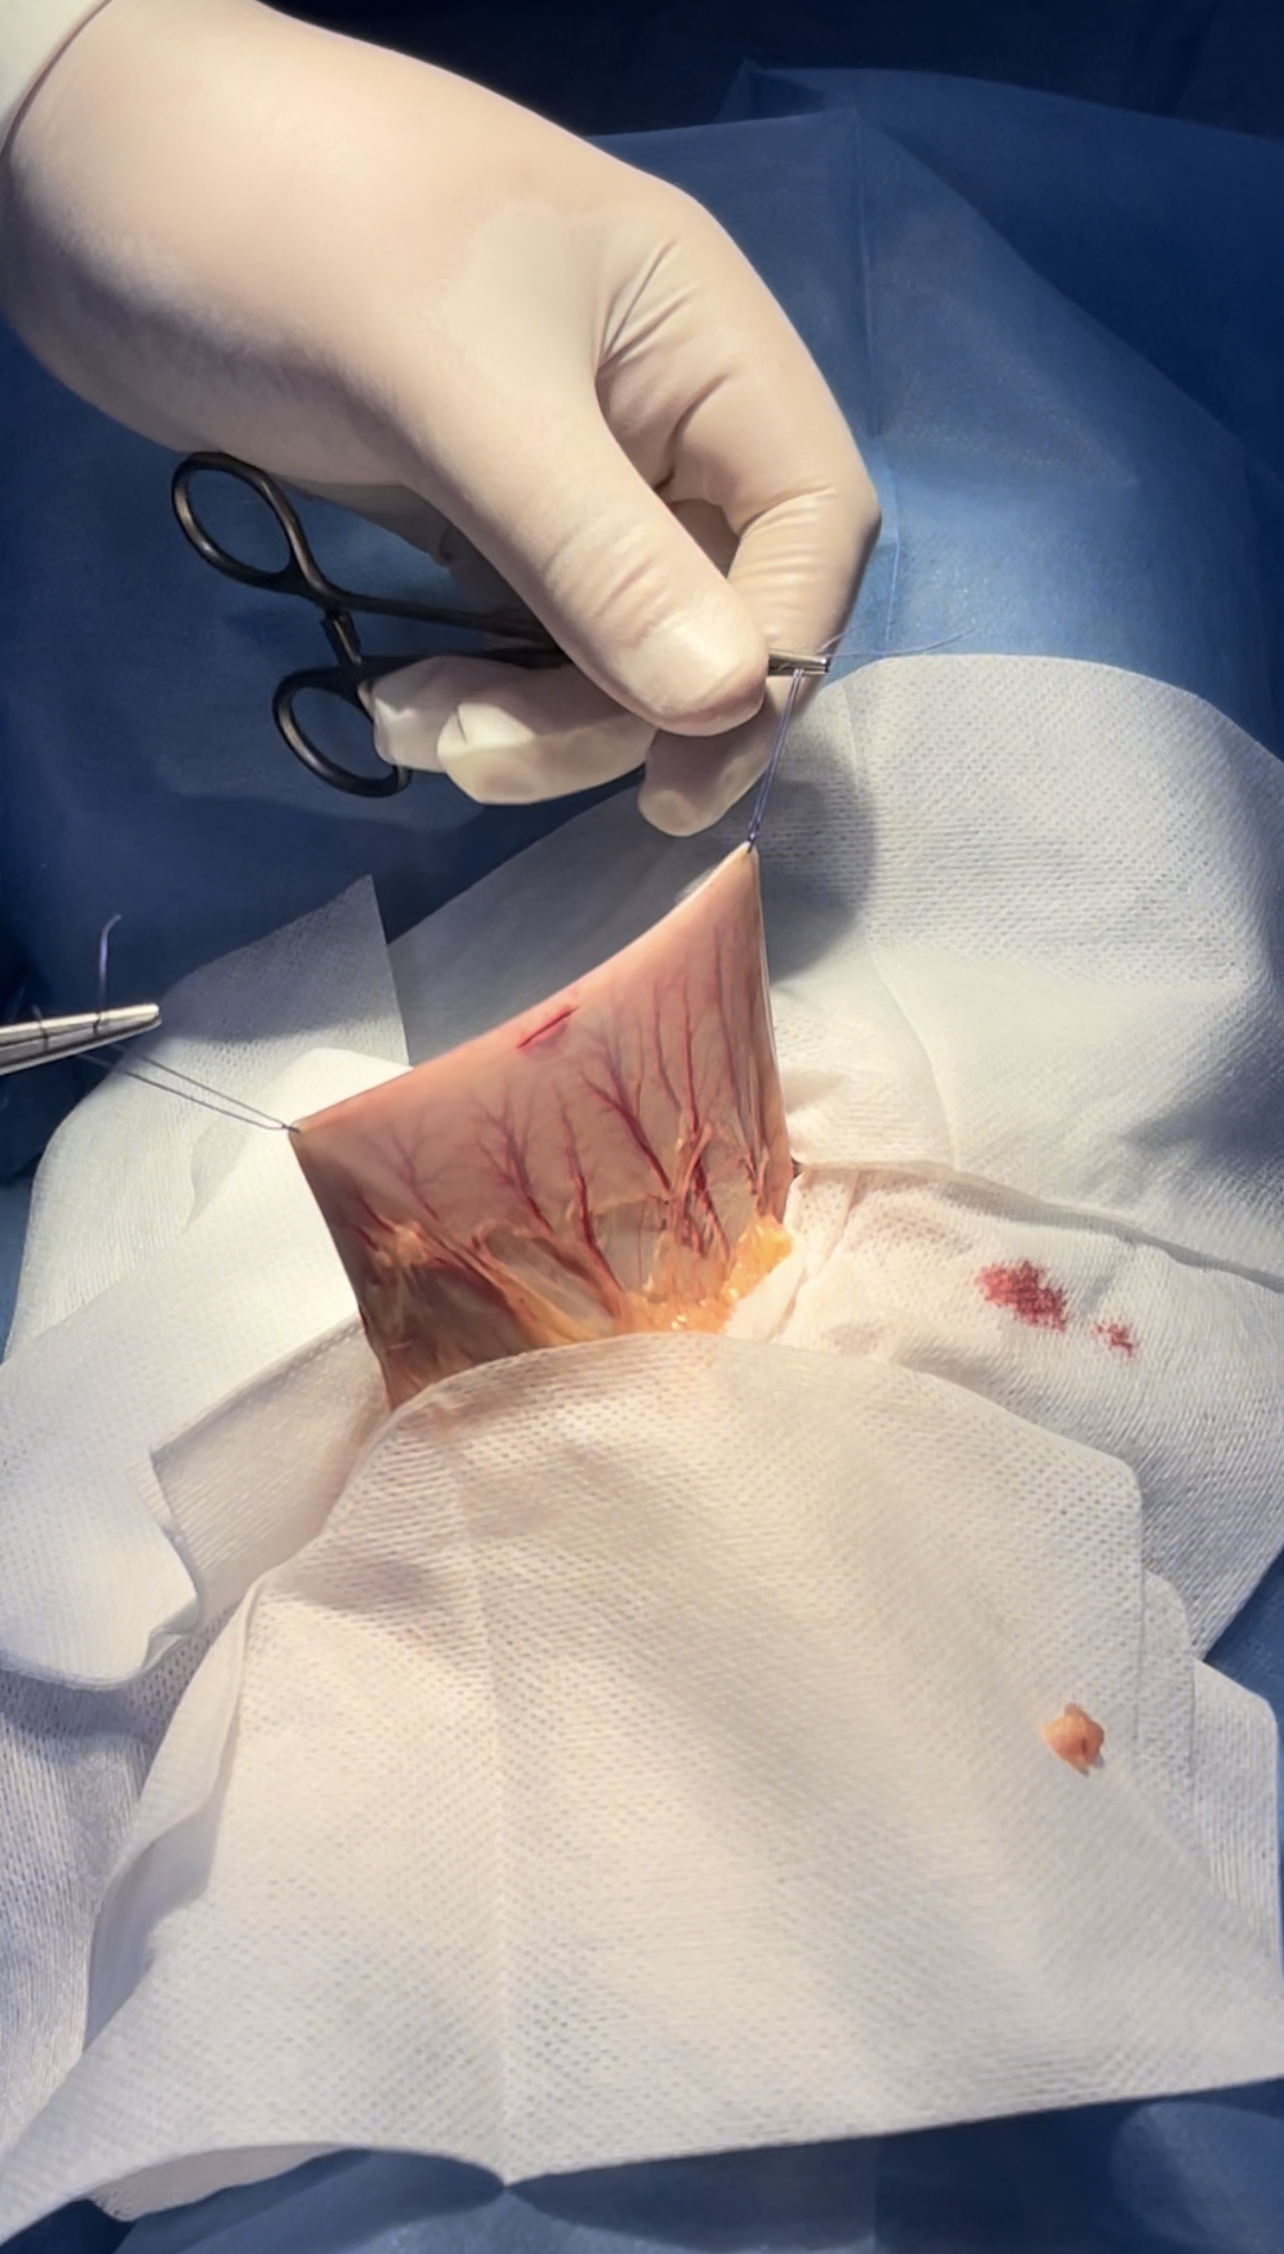

Ventral midline incision extended from the xiphoid to the umbilicus

Fb causing improper emptying of the stomach

Isolation preventing contamination of the field

Stay sutures are helpful in organ manipulation

incision site between the greater & lesser curvature avoiding vasculature

Stapp incision is primary made

further more extension is made as needed

Removal of the clogged hair clumps